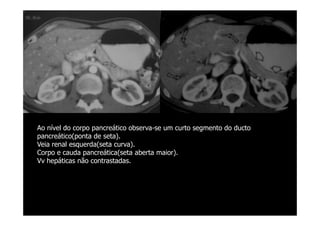

Ao nível do corpo pancreático observa-se um curto segmento do ducto

pancreático(ponta de seta).

Veia renal esquerda(seta curva).

Corpo e cauda pancreática(seta aberta maior).

Vv hepáticas não contrastadas.